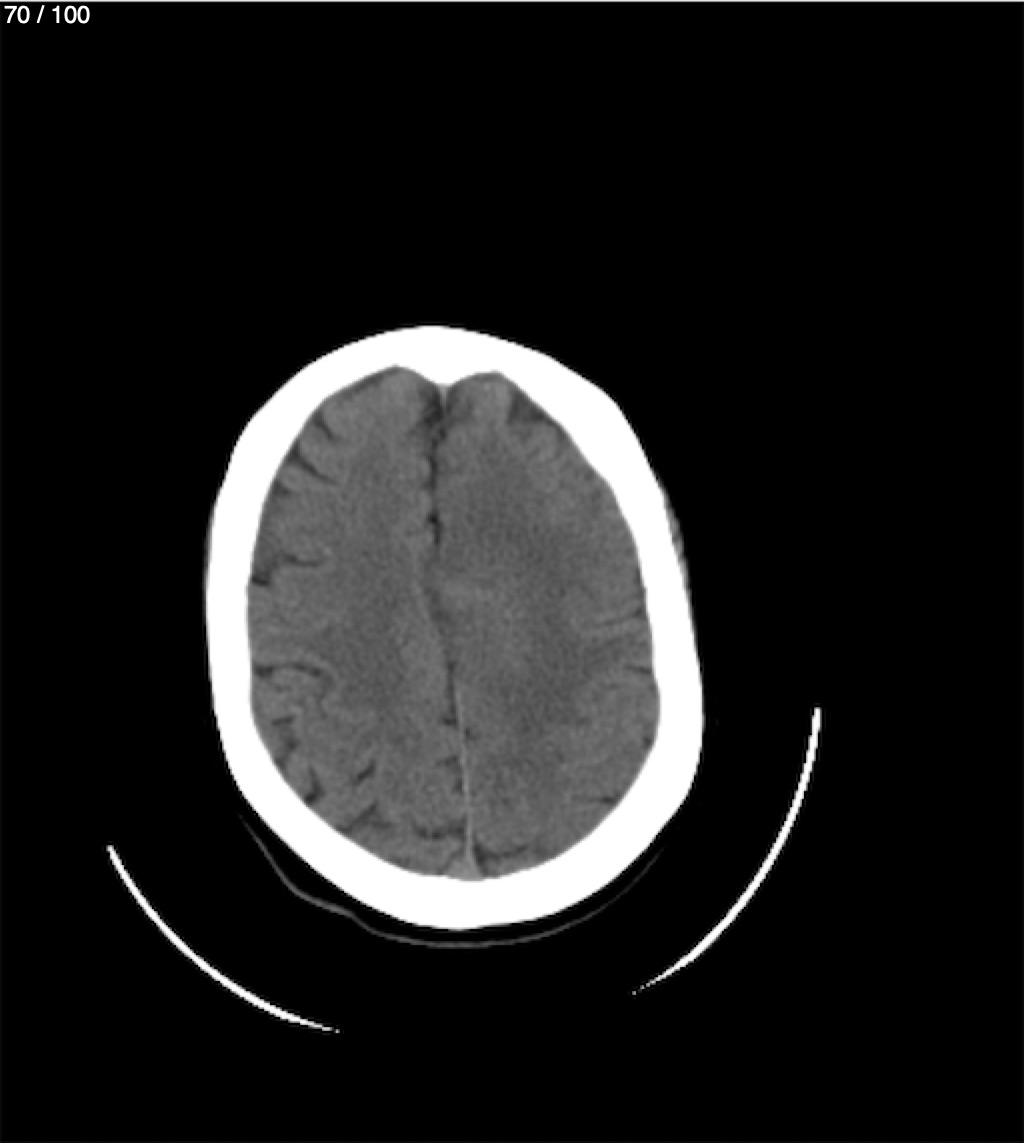

Valentin Perez Gomez 69A - T.C Craneo